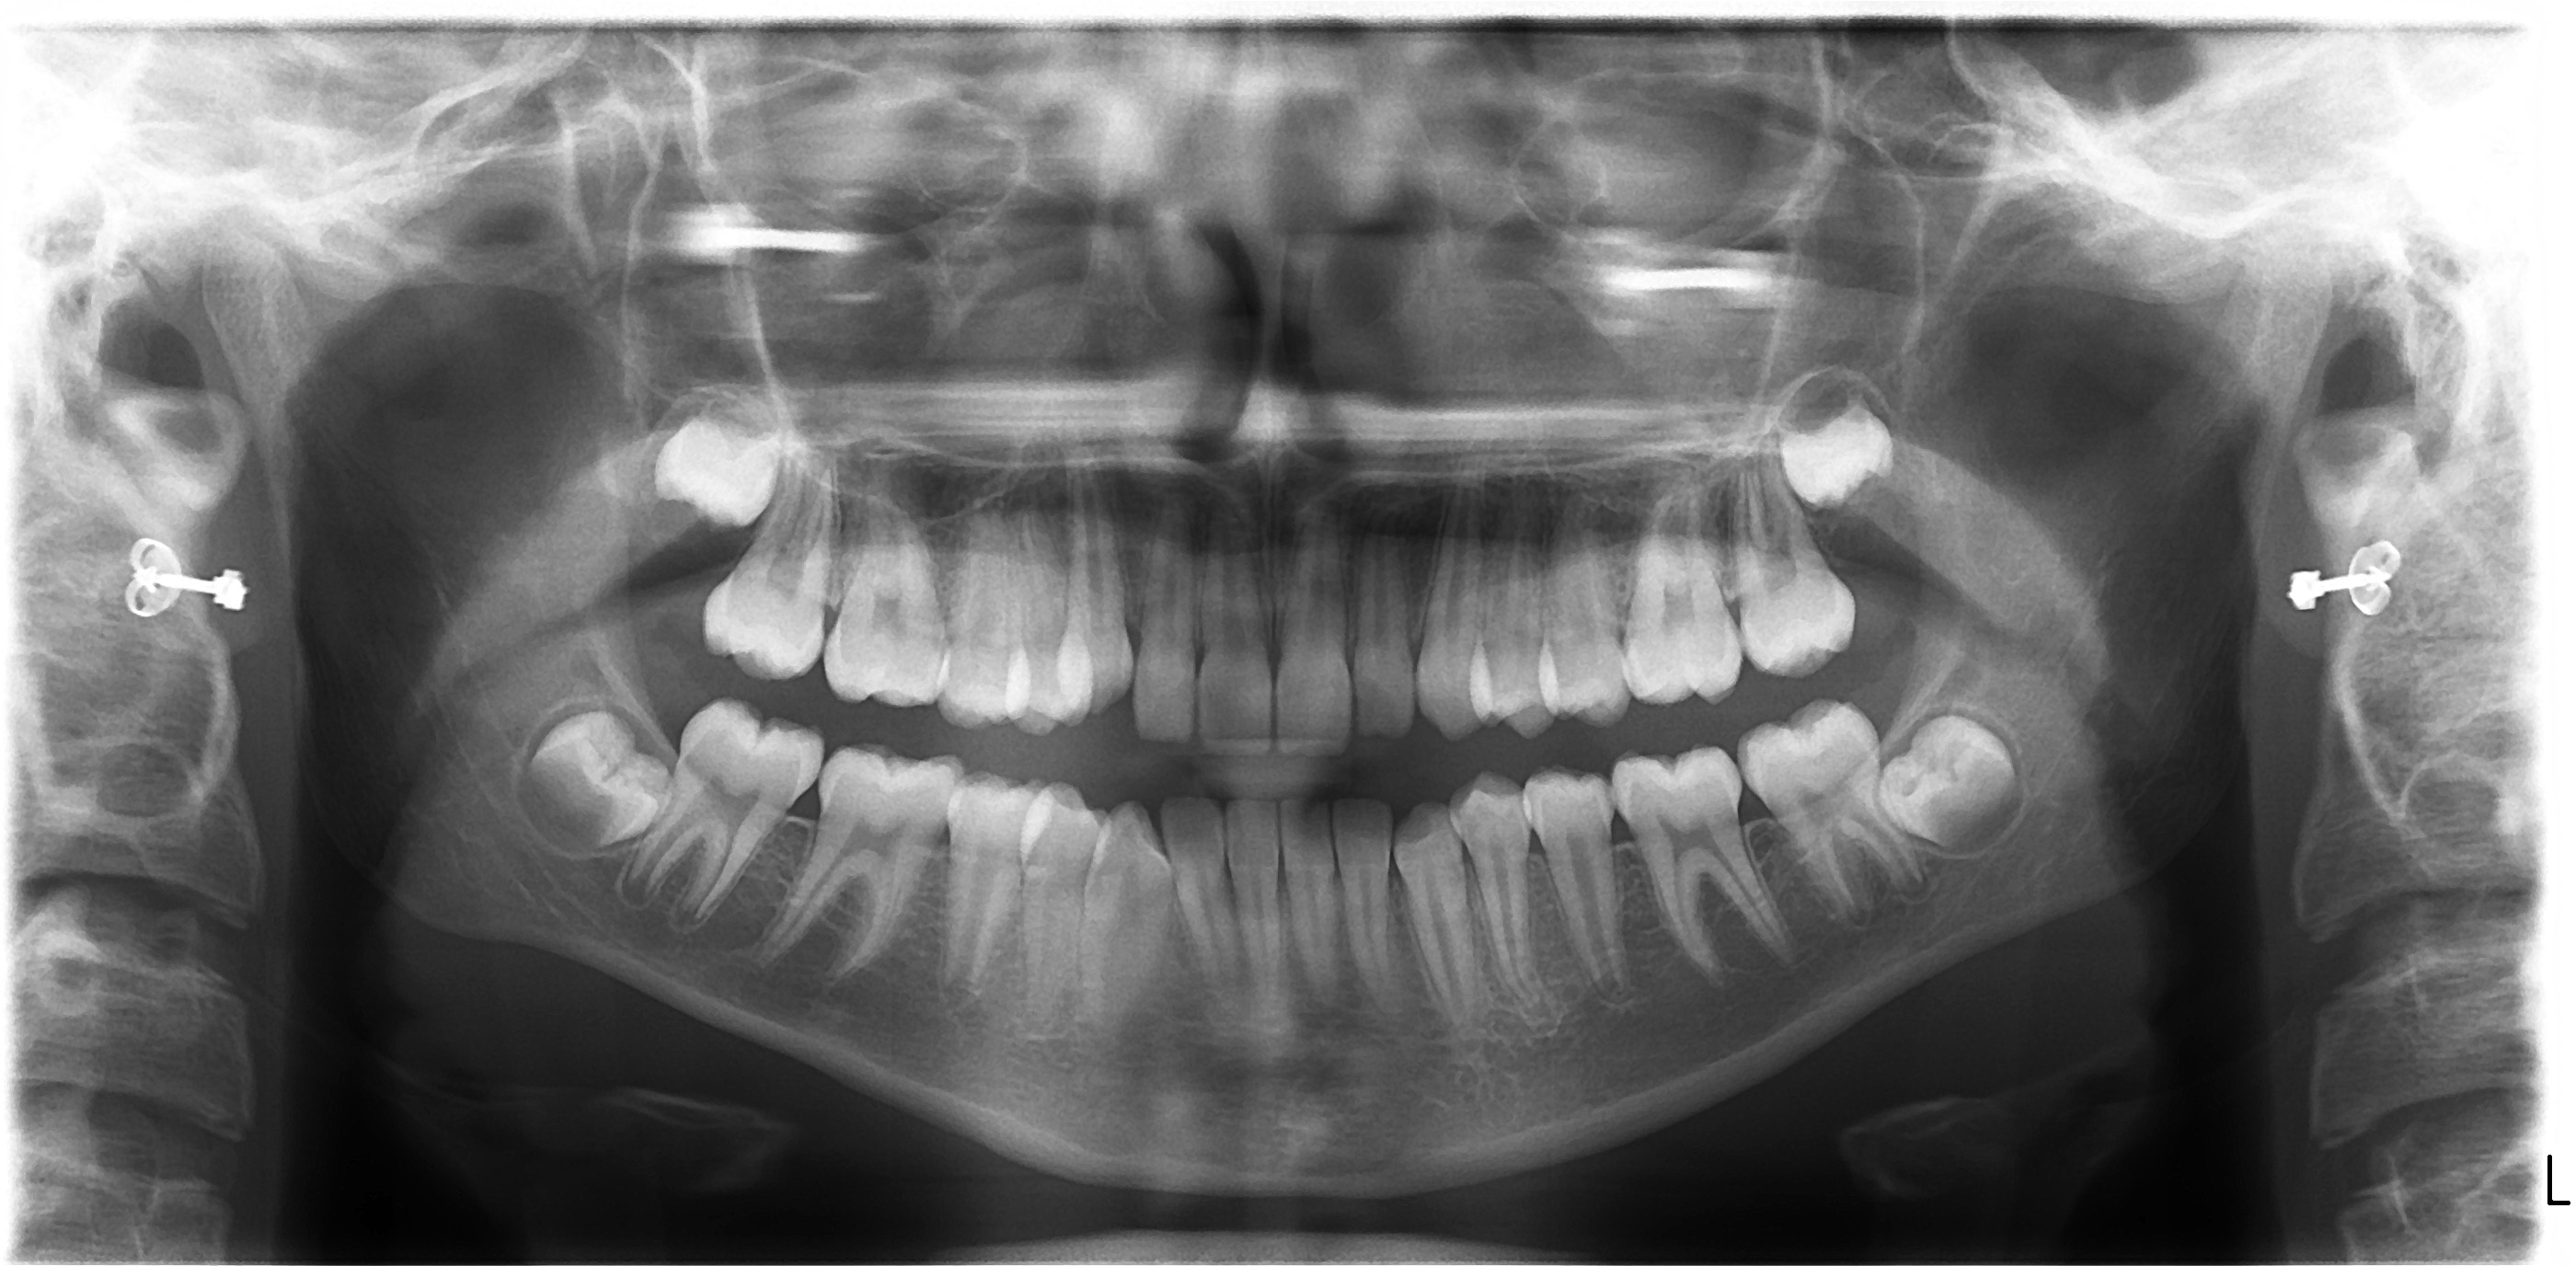

Unilateral Class II Malocclusion

The upper dental midline deviates to the left (Fig.2,4). Facial profile is normal (Fig.3). The right molar relationship is Class II (Fig.5), while the left one is normal or slightly Class III (Fig.6). How to treat?